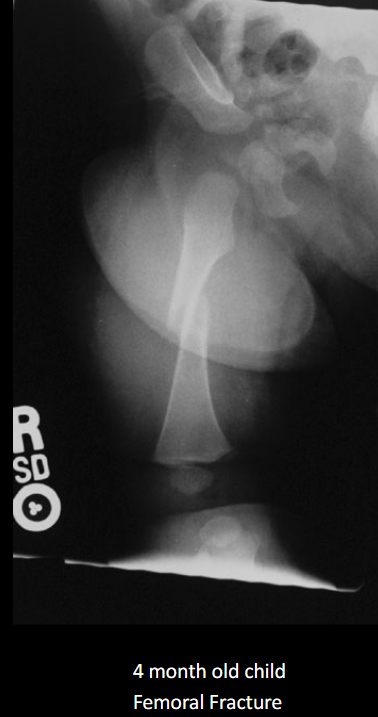

Define NAI.

Non-accidental injury/trauma; deliberate physical harm to a child.

Classic metaphyseal injury in NAI?

Corner/bucket-handle fracture.

Why are posterior rib fractures suspicious for NAI?

From squeezing the thorax.

Preferred initial imaging in suspected NAI?

Skeletal survey (not a ‘babygram’).